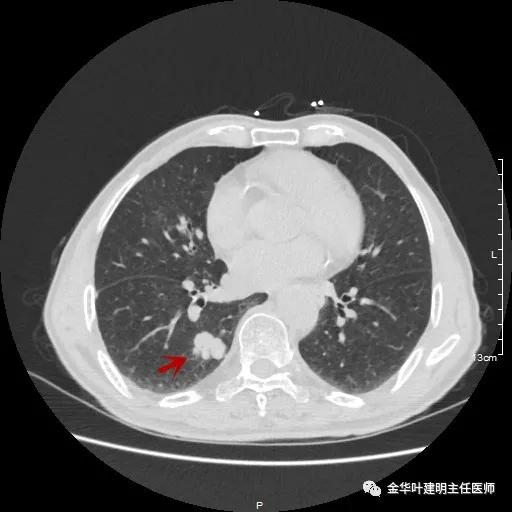

以上示右肺中叶病灶3。是混合磨玻璃结节,位置差,邻近肺门部,无法局部楔形切除,抗炎治疗后靶扫描显示了更清楚的细节,是典型的肺癌影像特征(此处未另提供)。从单病灶来看,需要行右肺中叶切除并清扫淋巴结才能得以治疗。

以上示右中叶病灶4。也是囊腔型病灶,病灶大,囊壁是磨玻璃密度,亦是较为典型的囊腔型肺癌影像。单病灶看,需中叶切除来治疗,因病灶3的存在,中叶切除可同时解决病灶3与病灶4。